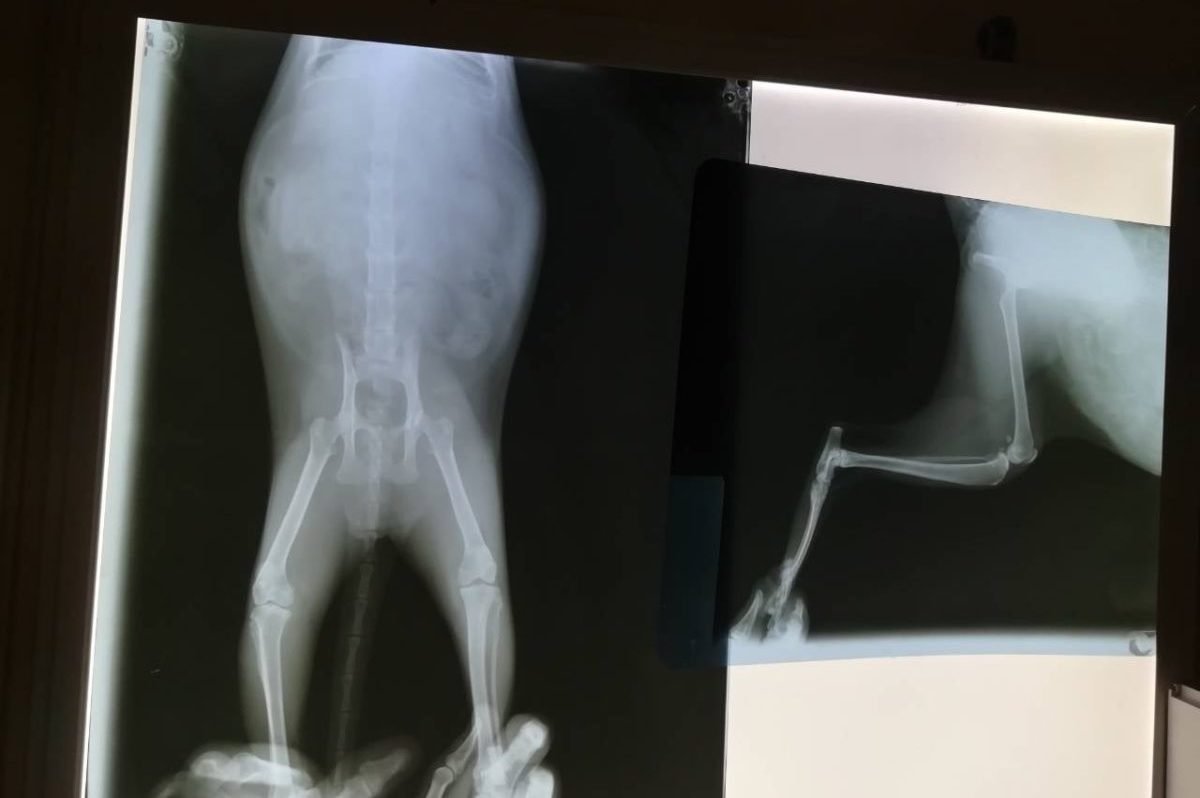

"У нее еще и опухоль на груди. На улице Тесла прожила бы меньше суток, а дальше - мучительная гибель. По анализам - явная анемия, она все время старается закрыть свои больные глазки. Срочно начали колоть препараты железа, терапия интенсивная. Диагноз не утешительный: атаксия центрального происхождения, повреждения седалищного нерва , кальцевирус, гнойный хламидиоз глаз, вследствие заворота век язвы на роговице, пиометра (гнойное воспаление матки) с осложнениями. Мы не можем ее бросить. Но и лечить нечем, потому что нет средств. Пожалуйста, помогите ее спасти", - написала Ольга Уманчик, волонтер мини-приюта «Мы за право на жизнь».

Сейчас оплачен только рентген в трех проекциях. Клиника лечит в долг, но его нужно срочно отдавать. В приюте находится очень много "срочников", поэтому рисковать доброжелательностью врачей волонтеры не могут. Впереди кошечку ждет минимум месяц лечения, даже пара гривен от каждого из нас может помочь ей выжить. Реквизиты на оплату указаны в посте в группе приюта в Facebook. Если у вас есть какие-то вопросы, можете уточнить информацию здесь или связаться с Ольгой по телефону напрямую: (093) 235-03-70.